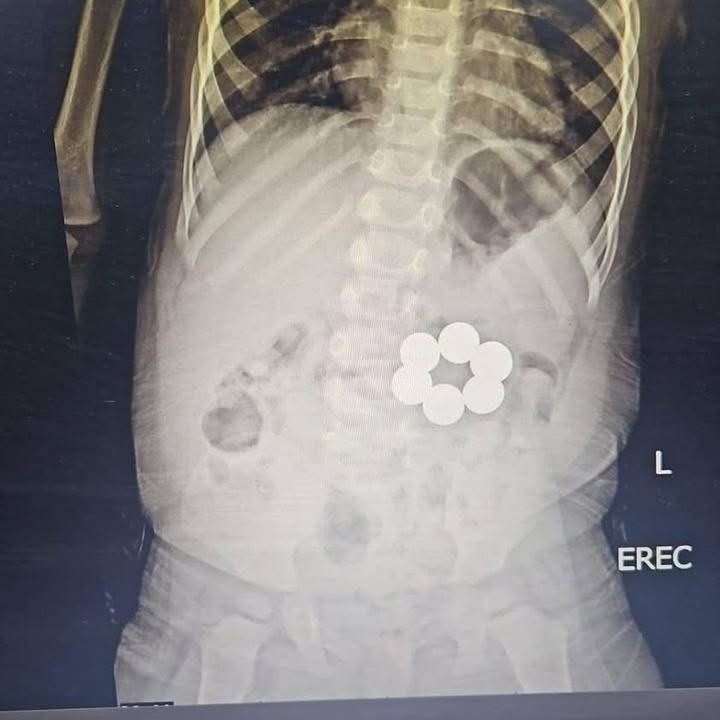

أفادت جامعة المنصورة بمحافظة الدقهلية أن الطفل وصل إلى المستشفى وهو يعاني من أعراض مقلقة استدعت التدخل الطبي العاجل، حيث كشفت الفحوصات والأشعة التشخيصية عن وجود قطع مغناطيس داخل الجهاز الهضمي، ما شكّل خطرًا كبيرًا نتيجة احتمالية التصاقها عبر جدران الأمعاء، وهو ما قد يؤدي إلى حدوث ثقوب أو انسداد معوي ومضاعفات خطرة.

وتمكن الفريق الطبي من استخراج القطع المغناطيسية الست بنجاح باستخدام المنظار خلال وقت قياسي، دون تسجيل أي مضاعفات، مع الحفاظ الكامل على سلامة الجهاز الهضمي للطفل، الذي غادر المستشفى في حالة صحية مستقرة.